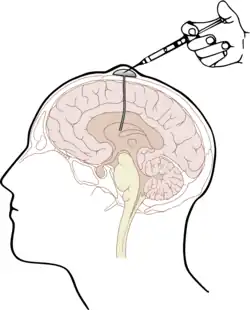

Die naheliegendste Form des Wirkstofftransportes in das ZNS unter Umgehung der Blut-Hirn-Schranke stellt die Injektion direkt in den Liquor cerebrospinalis (intrathekal) oder direkt in die Hirnventrikel (intraventrikulär)[11] dar. Der Wirkstoff wird dabei direkt in den Liquor injiziert. Angewendet wird dieses Verfahren beispielsweise als intrathekale Chemotherapie[12][13] unter anderem mit dem Folsäure-Antagonisten Methotrexat (MTX), mit Cytarabin (AraC) und Cortisol; speziell bei Patienten mit akuter lymphatischer Leukämie und aggressiven Lymphomen.[14] Die drei Wirkstoffe werden in der triple intrathecal chemotherapy zur Behandlung der Hirnhaut-Leukämie[15] zusammen in den Liquor appliziert.[16]

Die intrathekale Wirkstoffapplikation ist – verglichen mit der intravenösen (systemischen) Gabe von Wirkstoffen – deutlich aufwändiger und für viele Patienten auch unangenehmer. Darüber hinaus bestehen bei derartigen Darreichungsformen aufgrund der deutlich erhöhten Infektions- und Verletzungsgefahr besonders strenge Anforderungen an Hygiene und technische Fertigkeiten des Anwenders. Durch die Injektion von Wirkstoffen mit Depotwirkung (slow release) können die Behandlungsintervalle auf längere Zeiträume – beispielsweise 14-täglich – gestreckt werden.[16] Weniger aufwändig ist die Verwendung eines Ommaya-Reservoirs, das unter die Kopfhaut implantiert wird. Einen ähnlichen Ansatz bieten implantierbare Medikamentenpumpen.[17] Bei schweren Schmerzzuständen kann diese Methode beispielsweise für die Dosierung von Morphin gewählt werden.[18][19] Auch zur Behandlung von Spastiken, beispielsweise bei Multipler Sklerose mit Baclofen, kann der Wirkstoff über eine solche Pumpe intrathekal appliziert werden.[20][21][22] Die Methode wurde erstmals 1984 angewendet[23] und ist seitdem etabliert.[24][25]